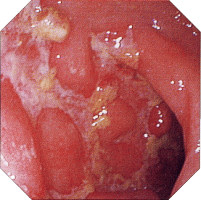

内視鏡所見

初期病変 アフタ様びらん アフタ様潰瘍

クローン病 クローン病画像 クローン病画像

提供:牧山和也先生

縦走潰瘍 敷石像 不整形潰瘍

クローン病画像 クローン病画像 クローン病画像